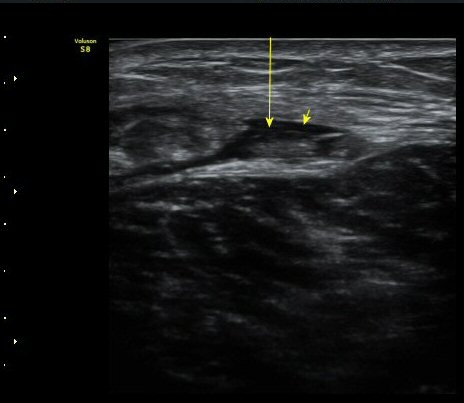

ºñº¹±Ù Ⱦ´Ü¸é°Ë»ç¿¡¼­ ºñº¹±Ù ³»Ãø, °¡Àڹٰ̱ú Á¢ÇÕ ºÎÀ§ÀÇ ÆÄ¿­°ú ¼ö¾× Àú·ù°¡ °üÂûµÊ(±×¸² 4)